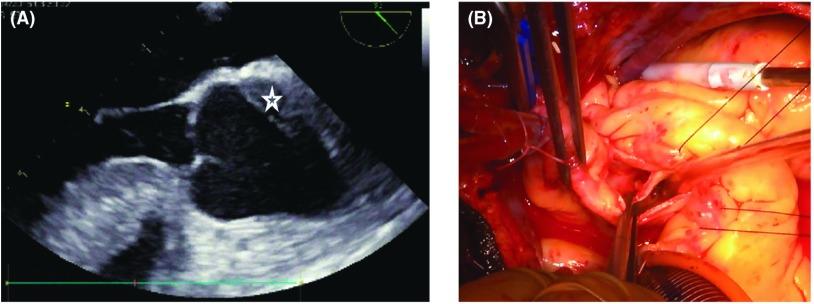

We report a case of a 48-year-old patient who developed localized aortic dissection of the left coronary cusp complicated by critical malperfusion of the LMT of the coronary artery. After percutaneous coronary intervention (PCI) for the LMT, a Koster-Collins-like direct repair of the localized aortic dissection was carried out by closure of the false channel using BioGlue (CyroLife, Inc., Kennesaw, GA, USA) with the reinforcement of double Teflon felt strips.

我们报告一例48岁患者,发生左冠状动脉瓣叶局限性主动脉夹层,并发冠状动脉左主干严重灌注不良。在对左主干进行经皮冠状动脉介入治疗(PCI)后,采用类似Koster-Collins的直接修复方法,使用BioGlue(美国佐治亚州肯尼索市CyroLife公司)封闭假腔,并加用双层特氟龙毡条进行加固,对局限性主动脉夹层进行修复。